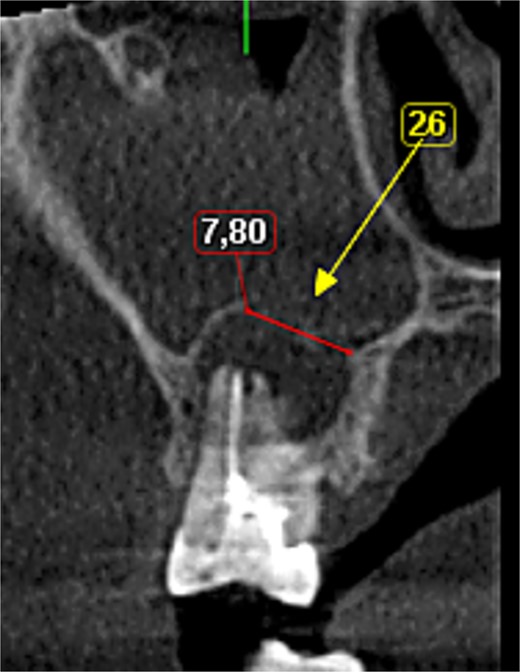

A 56-year-old female patient without any systemic diseases was referred by otolaryngology for evaluation by oral surgery due to presenting pain on the left side of the face for two weeks. The patient’s first molar presented a wide restoration (Fig. 1). This molar had undergone endodontic treatment some years ago. The CT scan showed a hyperdense left maxillary sinus almost entirely with loss of continuity of the maxillary sinus floor at the level of the left upper first molar involving the furcation zone, it is evident an oroantral communication of 7 mm (Fig. 2). The patient referred to spontaneous pain during chewing. Based on the CT scan and the clinical findings, pharmacological management was indicated with oral antihistamine 10 mg every 24 hours for 10 days, Moxifloxacin 400 mg every 24 hours, and scheduled extraction with oroantral communication closure with collagen sponge on the third day after starting the antibiotic, which will be used for a total of 10 days. The patient agreed to sign an informed consent file to make the technique to extraction and close the oroantral communication.